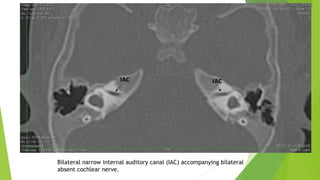

Bilateral narrow internal auditory canal (IAC) accompanying bilateral

absent cochlear nerve.